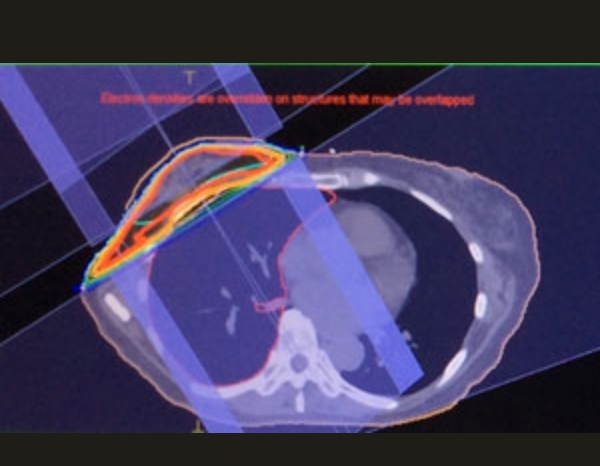

小肺がんの照射

肺がん+リンパ節

はじめのうちは、広く照射。その後、縮小照射正常肺にできるだけ当たらないように3個に分けて照射